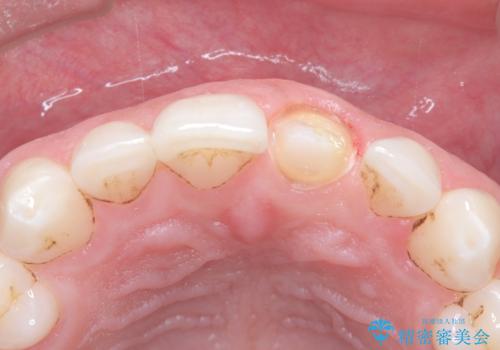

過去に神経の治療をした歯に変色がみられました。ラバーダム防湿の重要性を説明し、予防的に再根管治療から行い、被せ物をすることとなりました。

なるべく隣の歯と調和するようにしました。大変ご満足いただけました。